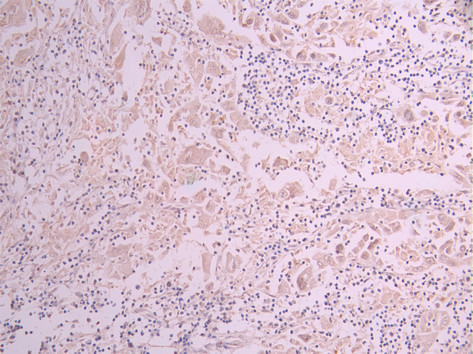

IHC image of CSB-RA283068A0HU diluted at 1:100 and staining in paraffin-embedded human skeletal muscle tissue performed on a Leica BondTM system. After dewaxing and hydration, antigen retrieval was mediated by high pressure in a citrate buffer (pH 6.0). Section was blocked with 10% normal goat serum 30min at RT. Then primary antibody (1% BSA) was incubated at 4°C overnight. The primary is detected by a Goat anti-rabbit polymer IgG labeled by HRP and visualized using 0.05% DAB.